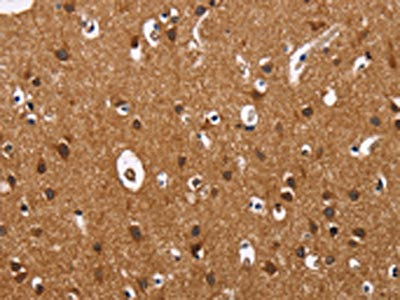

The image on the left is immunohistochemistry of paraffin-embedded Human brain tissue using CSB-PA941698(ILK Antibody) at dilution 1/60, on the right is treated with fusion protein. (Original magnification: ×200)